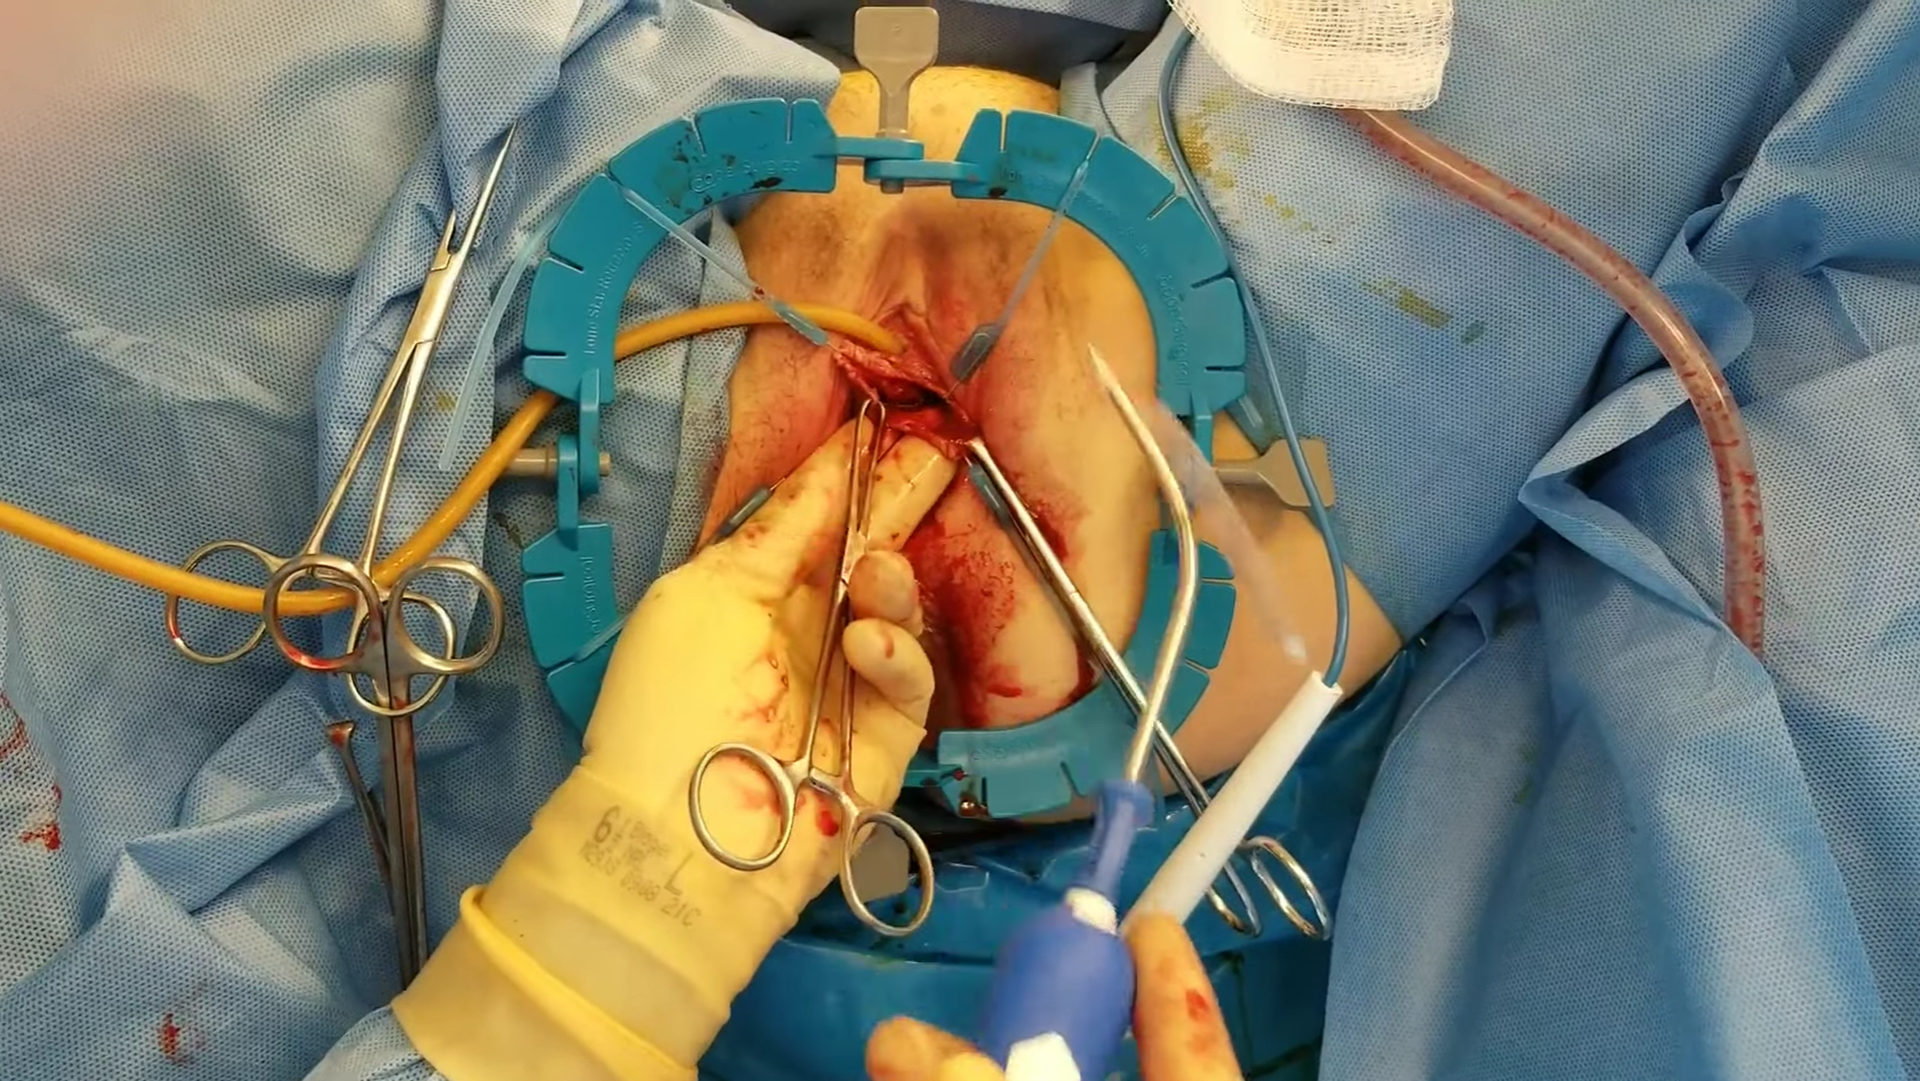

Cilt Grefti Uygulaması

Cilt Grefti Uygulaması

Cilt Grefti Uygulaması